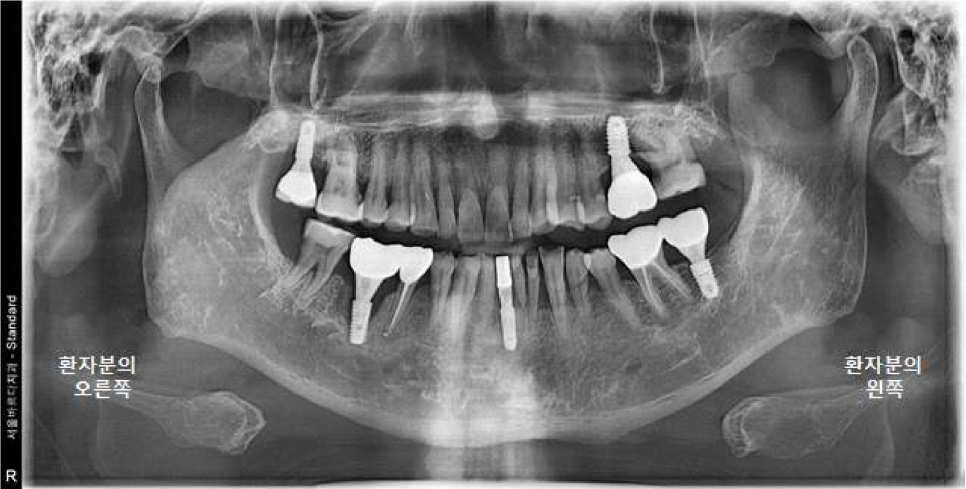

파노라마 엑스레이 상에서 좋지 않게 보이는

오른쪽 아래 어금니도 같이 설명드렸습니다.

엑스레이상으로 보면 뿌리에 길게 신경치료 한 부분이 보이고

"뿌리 끝 염증으로 주변 뼈가 까맣게 녹고 있는 모습"이 보입니다.

왼쪽 위 큰어금니 (26번치아) : 임플란트

오른쪽 아래 큰어금니 (46번치아) : 발치 + 임플란트 + 뼈이식

파노라마 엑스레이랑 3차원 CT 사진을 보시면

아주 잘 심어진 상태를 보실 수 있습니다.

염증이 없는 상태여서, 뼈이식 없이 즉시 임플란트 식립을 진행 하였습니다.

수술 후, 초기고정력도 높게 잘 나왔습니다.

다음 날, 오른쪽 아래 큰어금니 수술을 진행하였습니다.

완료된 파노라마 엑스레이 사진입니다!

왼쪽 오른쪽 교합도 잘 맞으니 부드러운 음식부터 식사 잘 시작해보시고,

불편사항 생기시면 미리 전화 주시고 내원하시기로 하셨습니다.